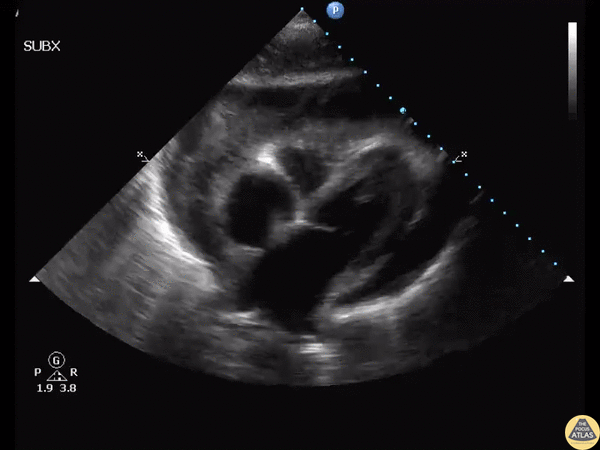

A male in his 20’s presented following failed community acquired pneumonia treatment with fever, chest pain, and soft vitals. Bedside ultrasound revealed purulent pericarditis visible in this subcostal window. CT showed LLL pneumonia with empyema. Image courtesy of Robert Jones DO, FACEP @RJonesSonoEM Director, Emergency Ultrasound; MetroHealth Medical Center; Professor, Case Western Reserve Medical School, Cleveland, OH View his original post here